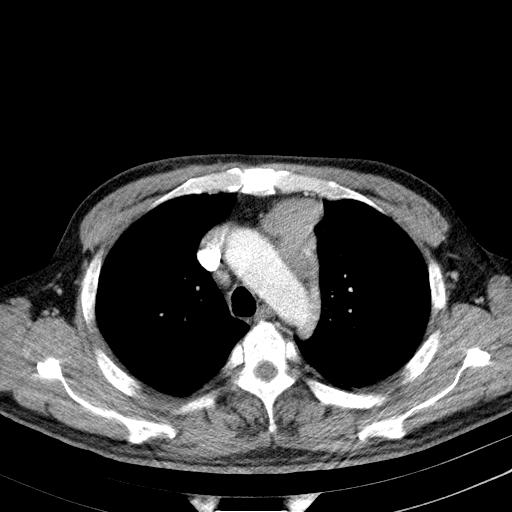

先行ct平扫,纵膈内多发软组织影,ct值约为36hu,以下为增强扫描和腹部平扫。

请会诊